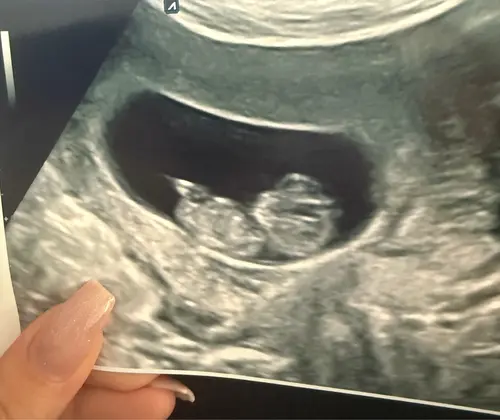

Beetje off-topic maar ik heb met 8 weken een echo gehad en ben nu 10 weken ...

Nee inderdaad was heel bijzonder. 😊 Bij 7 weken was er nog niet zoveel te zien. En dan ineens zo'n baby'tje